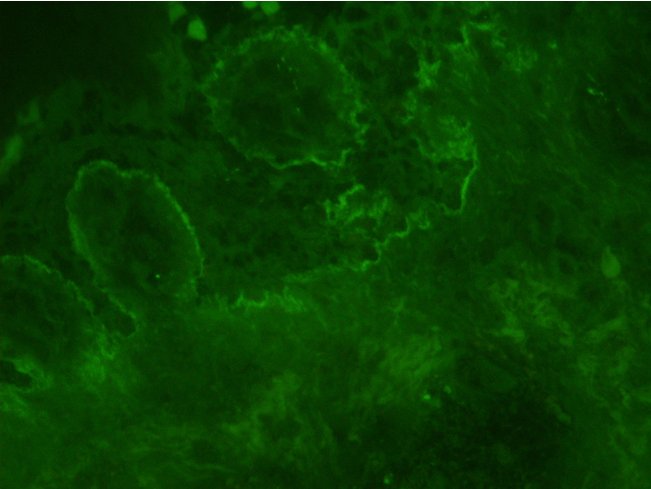

Two 6-mm punch biopsy were obtained from 2 separate lesions that demonstrated mixed superficial perivascular and interstitial dermatitis including many neutrophils. The dermoepidermal junction showed vacuolization of basal keratinocytes. Numerous clustered 5 mm to 2 cm clear smooth vesicles and tense bullae on the palmar surface with no nail involvement appreciated (Figure 3). The dermoepidermal junction of the lesion showed vacuolization of basal keratinocytes (Figure 4). Visualization under direct immunofluorescence (DIF) showed linear IgA deposit in the basement membrane zone (Figure 5).

Figure 5: Visualization under direct immunofluorescent microscopy (DIF) showed linear IgA deposit in the basement membrane zone.